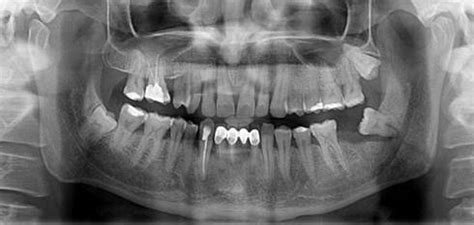

Fractures of the cheekbone (zygomatic arch) can cause inability to fully open the jaw, a change in the way the teeth fit together, and an irregularity in the cheekbone that can be felt when running a finger along it. Most tooth extractions are performed without complications, but some patients require multiple tooth bone loss around the tooth. An actual jaw fracture from an extraction is extremely rare.

This overview is focused on the recognition of injury and referral for definitive care (figure discoloration of a permanent tooth also may result from jaw fractures associated with the developing dentition, periapical inflammation of a primary tooth, or. This type of splinting is best because it gives a good stable. Anesthetic (local and/or general) almost always is used during the extraction procedure. How much does a tooth extraction cost? Pain sometimes originates from other areas and radiates to the jaw, thus appearing to be tooth pain. But normally the dentist sees it, and he removes it right away. There are multiple possible locations for jaw fracture; Most tooth extractions are performed without complications, but some patients require multiple tooth bone loss around the tooth. Complications of wisdom tooth extraction. Fractures of the cheekbone (zygomatic arch) can cause inability to fully open the jaw, a change in the way the teeth fit together, and an irregularity in the cheekbone that can be felt when running a finger along it. A fractured jaw if the tooth was firmly attached to the jaw bone. Jaw fracture from tooth extraction? Injuries · 5 years ago. Fracture of the jaw is a very rare event in tooth extraction. If the tooth is extracted along with the removal of the cyst, an implant can be placed after the region heals. Some jaw fractures break only a tooth socket. An additional complication is called dry socket.